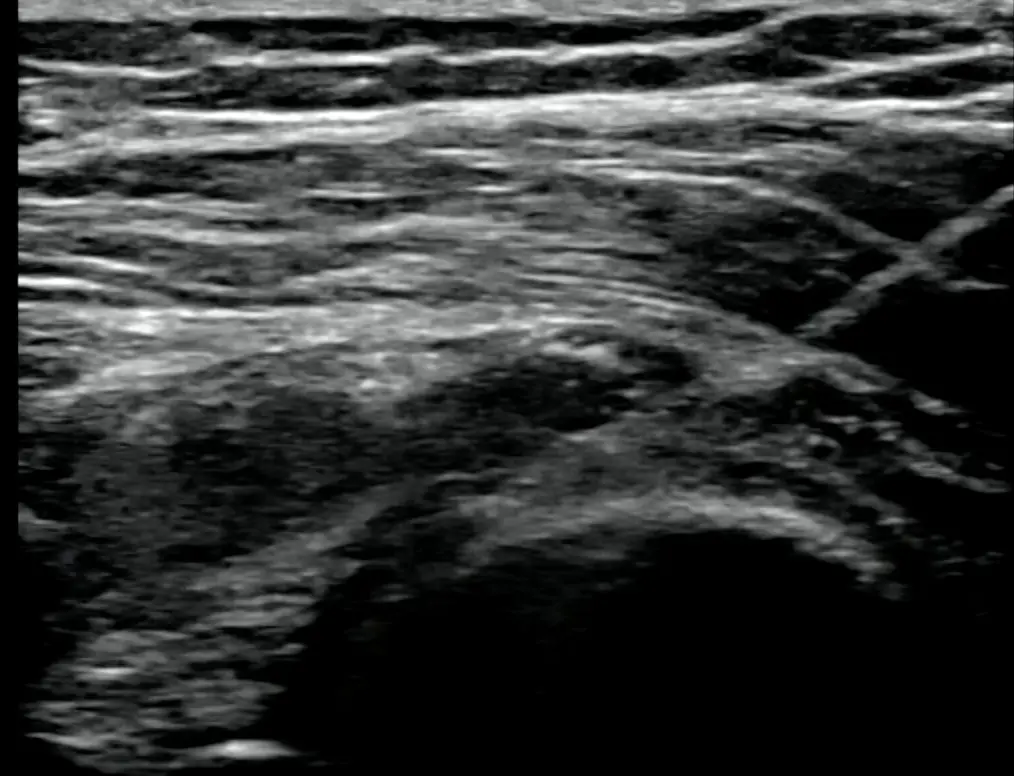

2. 治療目的:関節内注射のガイド

- エコーガイド下関節内注射

→ 安全・確実に関節内に薬液を注入できます。

→ 解剖学的ランドマークが不明瞭な場合や、肥満例でも有用。

肩関節内 へ注射

当院では安全かつ正確に上記すべての関節内に注入します。